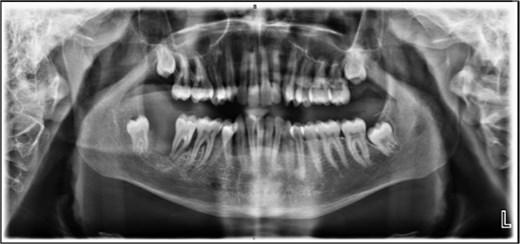

The patient was admitted from the clinic for urgent evaluation. Routine blood investigations were normal. An orthopantomogram revealed displacement of the second and third molars and a poorly defined superior margin of the alveolar process, suggesting osseous involvement (Fig. 2). Contrast-enhanced computed tomography (CT) of the facial bones and neck demonstrated a well-defined lucent lesion within the mandibular body with exophytic soft tissue extension into the oral cavity (Fig. 3). Magnetic resonance imaging (MRI) of the neck illustrated the hyperintense soft-tissue component with no rim enhancement or necrosis (Fig. 4). There was no lymphadenopathy noted clinically or radiograpgically.

XR OPG showing displacement of the second and third molars and a poorly defined superior margin of the alveolar process, suggesting osseous involvement